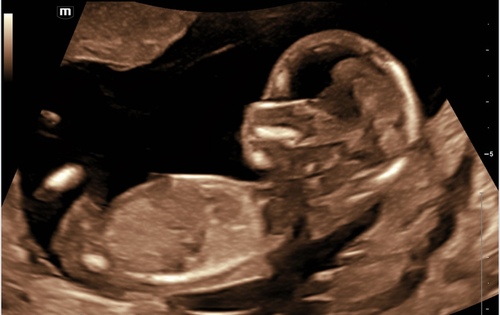

Deel hem hier nog een keer omdat er net een nieuw topic is geopend. 🩷 of 🩵 ?

Deel hem hier nog een keer omdat er net een nieuw topic is geopend. 🩷 of � ...

Ik denk een meisje.

Wat denken jullie?

Ik deel hem nog eens, de meningen zijn verdeeld… 💙🩷?